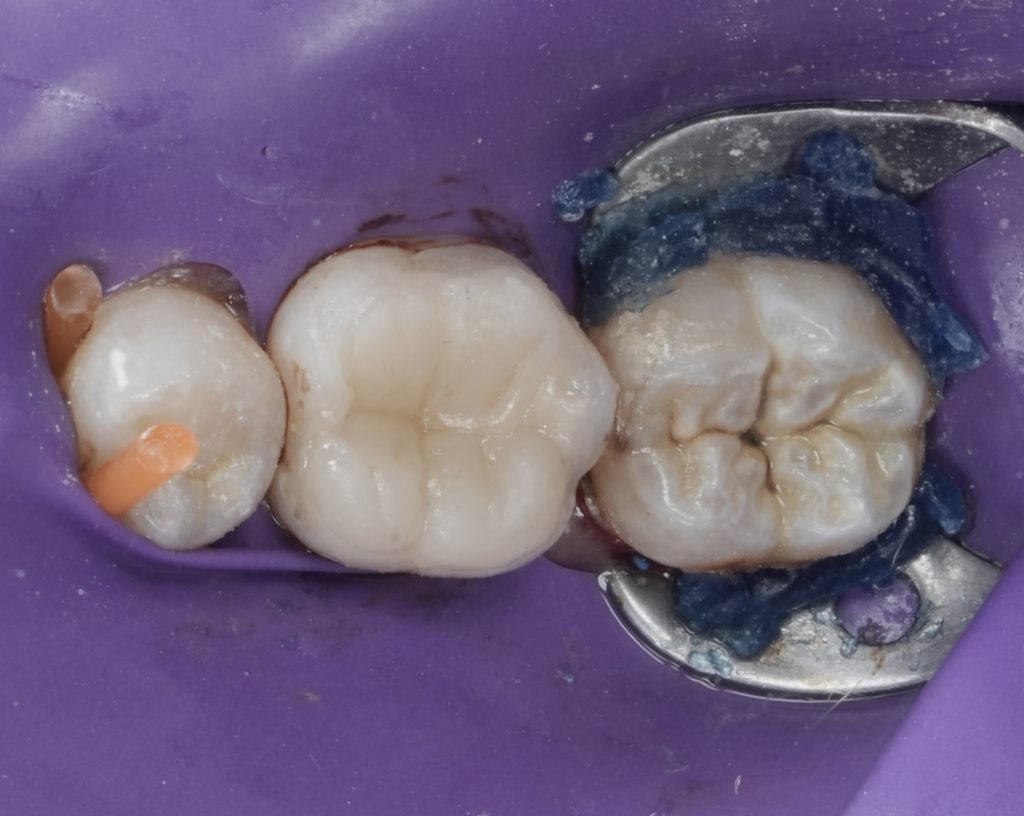

Cuspal Coverage Restoration

Given the extent of tooth structure loss and the functional demands on mandibular first molars, cuspal coverage was indicated. Occlusal anatomy was rebuilt using a biomimetic approach to restore:

- Functional cusp inclines

- Proper occlusal contacts

- Even stress distribution during mastication

Finishing and polishing were completed to achieve smooth margins and harmonious occlusion.

The final restoration provided:

- Complete canal disinfection and sealing

- Immediate coronal protection

- Reinforced cusps resistant to fracture

- Stable occlusion with functional anatomy

The tooth was returned to service with improved long-term prognosis.